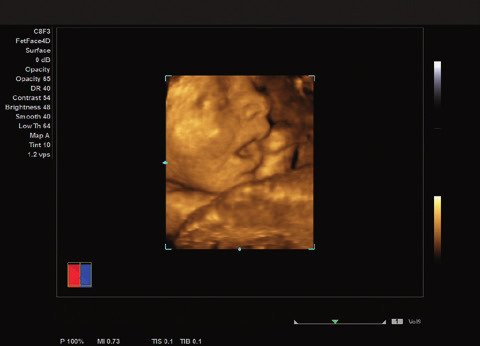

Das ACUSON NX2 Ultraschallsystem besitzt eine zukunftsfähige digitale Plattform mit nahezu unerreichter Bildqualität und sorgt für effiziente und zuverlässige Diagnosedaten. Die Vielseitigkeit des Ultraschallsystems wird mit einem großen kompatiblen Portfolio an Schallköpfen gedeckt, und so ist für jeden Anwendungsbereich etwas dabei. Die Bedienkonsole ist intuitiv aufgebaut und optimiert und erlaubt bis zu vier nach vorne gerichteten Schallkopfanschlüssen für eine enorme Effizienz und schnellen Workflow. So lassen sich bei der fetalen Bildgebung außergewöhnlich detailgetreue Darstellungen des Fetus im Gesicht zeigen oder durch die herausragende Farbdopplersensitivität bei der Darstellung der kleinen Gefäße des zystischen Schilddrüsenknotens kleinste Details erkennen. Weiterhin besticht das NX2 mit einfacher Aufrüstbarkeit bei wachsenden Anforderungen für Ihre zukünftigen Anwendungen und kompatible skalierbare Schallköpfe verringern ihren Kapitaleinsatz um bis zu 31 %.